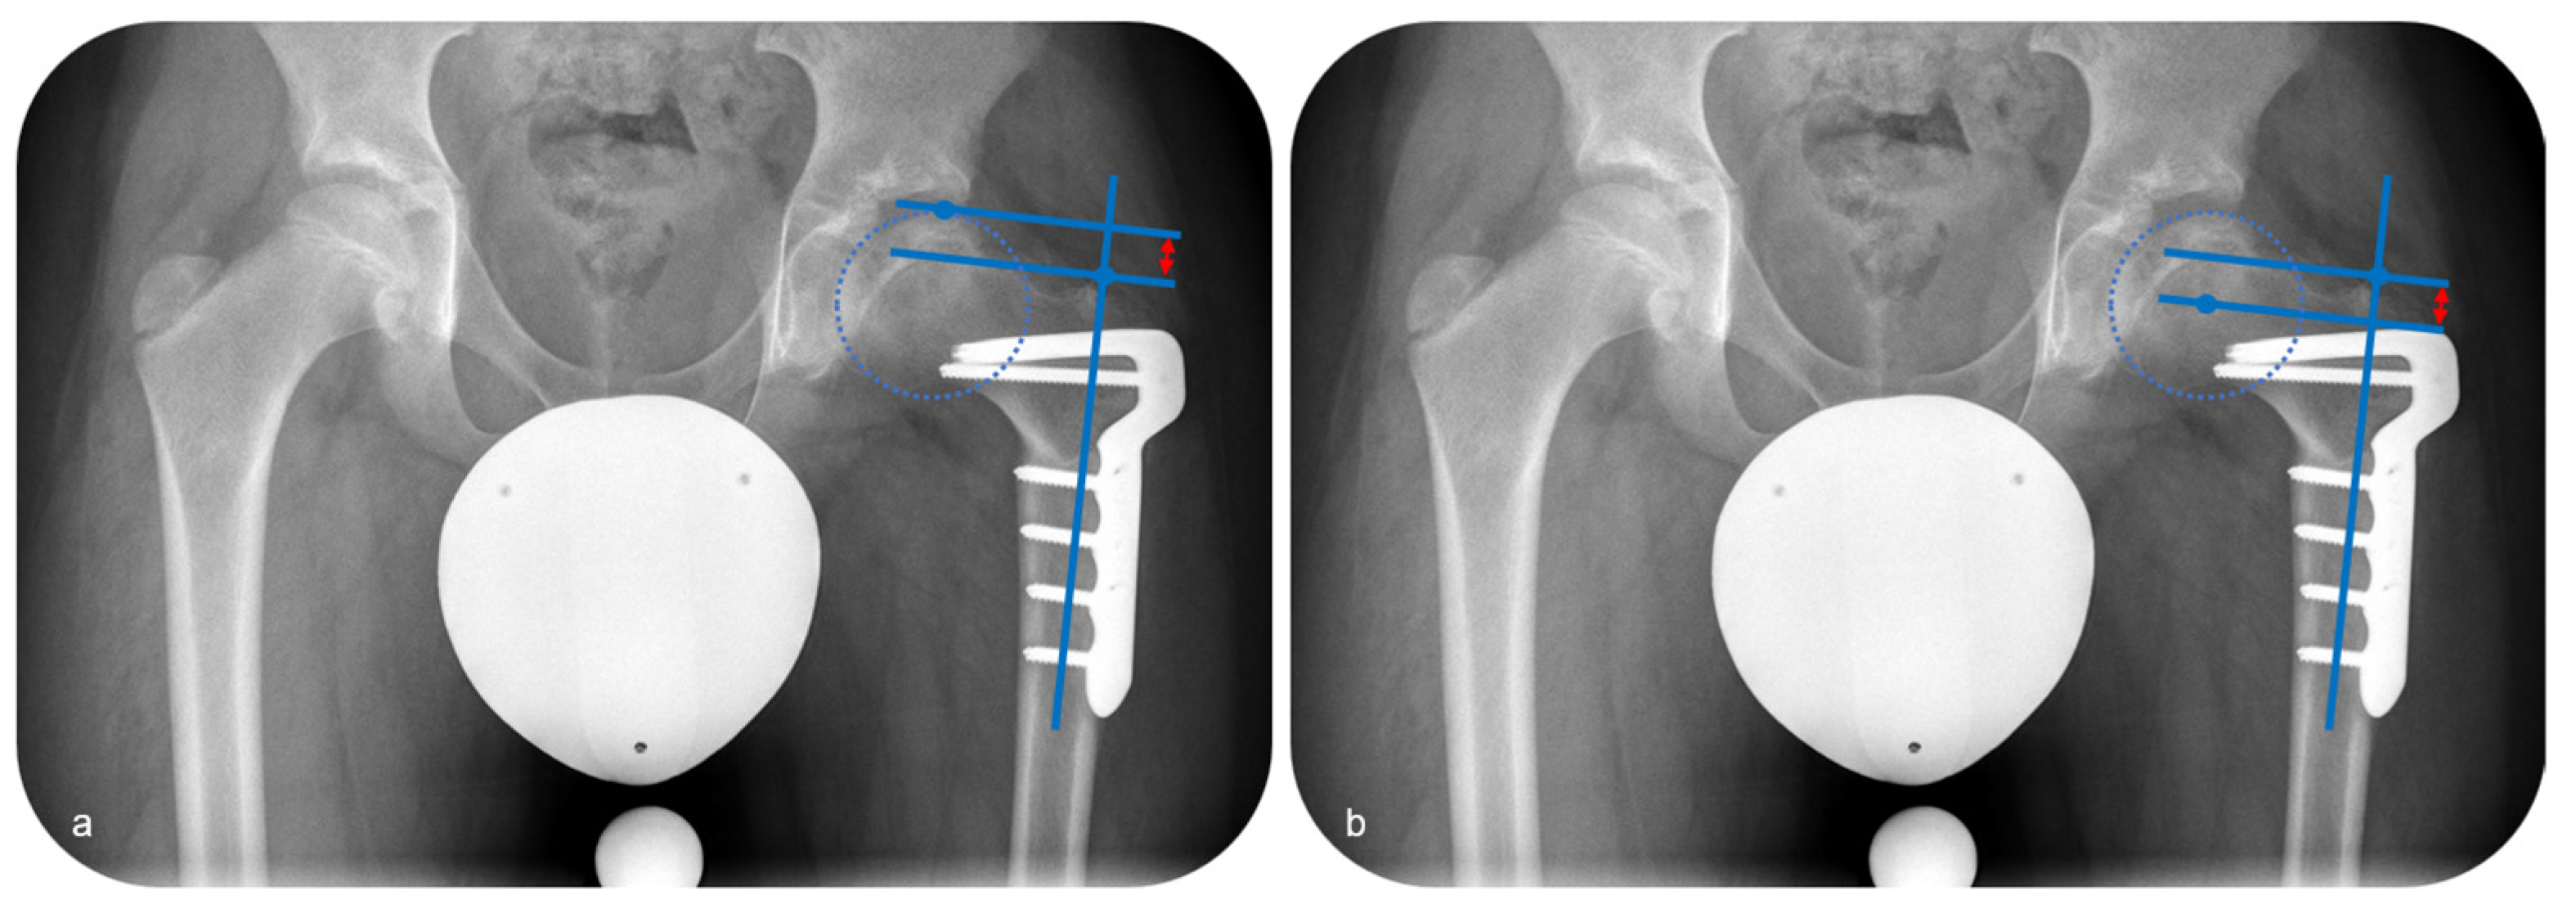

Anteroposterior and axial radiographs of the hip were analyzed preoperatively and at the last follow-up. The radiological evaluation was performed with regard to the stage of disease according to Waldenstroem, joint orientation and axis alignment with reference to established parameters [18]. The lateral pillar was assessed according to the Herring classification. For the children who reached the final stage of LCPD, the evaluation of the sphericity of femoral head was performed, taking the Stulberg classification into consideration. Concerning joint orientation, the medial proximal femoral angle (MPFA), the center-edge (CE) angle and the caput-collum-diaphyseal (CCD) angle were evaluated. The position of the tip of the greater trochanter in regard to the center of the femoral head was determined measuring the articulo-trochanteric distance (ATD) (Figure 5a) as well as the center head-trochanteric distance (CHTD) (Figure 5b).

The median MPFA was 100° (range, 83 to 103) preoperatively and 82° (range, 72 to 105) postoperatively with a median decrease of 13° (range, 3 to 29). The median CE angle was 15° (range, 6 to 23) preoperatively and 22° (range, 12 to 32) postoperatively with a median improvement of 7° (range, 0 to 20). The CE angle improved in eight of ten hips, while it did not change in two hips. The median CCD was 142° (range, 130 to 147) preoperatively, and 118° (range, 104 to 130) postoperatively, with a median decrease of the CCD of 18° (range, 11 to 41). The ATD increased in five and decreased in five hips, respectively. The median ATD was 17 mm (range, 15 to 24) preoperatively and 16 mm (range, 6 to 29) postoperatively. The median CHTD was 6 mm (range, 3 to 10) preoperatively and 8 mm (range, 0 to 12) postoperatively with a median increase of 2 mm (range, −4 to 6).

Figure 5. Measurement of the articulo-trochanteric distance ((a); red arrow) and the center head-trochanteric distance ((b); red arrow).